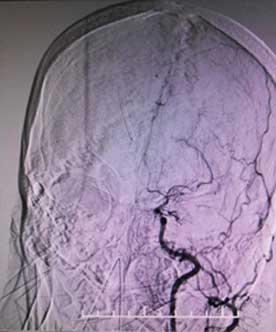

煙霧病又稱自發(fā)性腦底動脈環(huán)閉塞癥,是一組以雙側(cè)頸內(nèi)動脈末端和(或)大腦前動脈、大腦中動脈起始部緩慢進展性狹窄以致閉塞,腦底出現(xiàn)代償性異常血管網(wǎng)為特點的腦血管病。因其異常血管網(wǎng)在腦血管造影時形似“煙霧”,故稱為“煙霧病”。